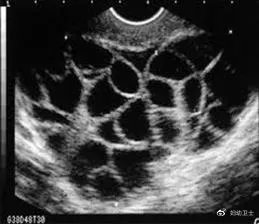

充满卵泡的卵巢

随之而来的潜在的风险就是OHSS。患有OHSS的女性,可能会有不同程度的腹胀、恶心、呕吐、腹泻、体质量快速增加、少尿或无尿、血液浓缩、血容量不足、电解质紊乱、胸腔积液、心包积液、腹腔积液、呼吸窘迫综合征,伴血栓形成倾向的高凝状态及多器官功能衰竭[2]。而且,增大的卵巢如果发生卵巢扭转或卵巢囊肿破裂、出血等并发症,必要时也要采取手术治疗,有可能影响女性的生育功能[3]。对于出现OHSS的“卵妹”,代孕机构会给一小笔钱作为“营养补偿”。但实际上,这点钱连看病都不够。